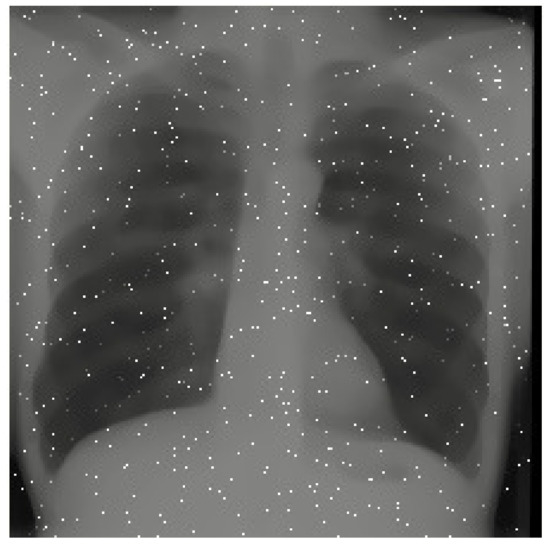

Ultimately, we decided to use another method very similar to Grad-CAM called Score-CAM because of its smoother, more consistent, and less noisy heatmaps [23]. Score-CAM finds the weights connected to individual pixels and filters of the image, thus finding which parts of the images have the most influence on the output of the CNN. Using Score-CAM, we generated heat maps of our X-rays that showcased the areas in the lung that xRGM-NET recognized as important for determining whether the patient was infected with COVID-19 or not. Areas in red represent opacities or spots in the lung that might indicate COVID-19 while areas in blue are parts that represent normality. As seen in Figure 7, the two COVID-19 positive patients have large opacities on the left sides of their lungs and these are shown in the Score-CAM images with dark red ovals. However, on the healthy patients, there is a distinct lack of these red markers and the lungs are shown to be healthy.

Figure 7.

Score-CAM on various X-rays. X-rays from [7,8].